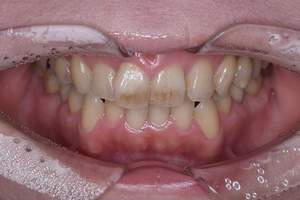

歯石除去

治療前

治療後

| 年齢 | 31歳・女性 |

|---|---|

| 主訴 | 主訴:歯石除去 部位:全顎 |

| 治療内容 | 初診検査・歯石除去 |

| 治療期間 | 2週間 |

| 費用 | 合計:約4,000~5,000円 内訳 初診料:約3,000~4,000円 (保険診療) 歯石除去:約1,000円 (2023年1月現在) |

| リスク・副作用 | ・歯肉の炎症がある場合は歯石除去中に出血を伴う可能性があります。 ・処置後に歯がしみることがあります。 ・歯茎の炎症が軽減すると歯茎が引き締まり、歯が長く見えることがあります。 |

| 治療方針 | 前歯部に叢生(歯列不正)があり多量の歯石が認められました。炎症の抑制を優先するため初診時はTBIのみ行い、2回目以降で歯石除去を行いました。今後は縁下歯石(歯ぐきの中に付着する歯石)の除去を全顎的に行っていく予定です。 |

| 担当者所見 | 叢生(そうせい)とは歯が折り重なるようにデコボコにはえている状態をいいます。歯ブラシが難しく磨き残しをしやすい為、普段使用している歯ブラシに加えワンタフトという細かい部分も磨くことのできる小さな毛束の歯ブラシの使用をおすすめしました。 |

| 担当者所見 | 歯石の存在は感じていたものの歯科医院に苦手意識が強く3年ほど放置していたとのことでした。 舌で触った時にザラザラすることや口臭も気になった為、今回意を決してご来院くださいました。 ブラッシング指導を熱心に聞いてくださり、セルフケアで歯肉の炎症を抑えた上で歯石除去ができたのでお痛みが少なく行えました。 患者様も苦手意識が克服できたと喜んでくださり、今後の治療にも積極的な姿勢です。 |